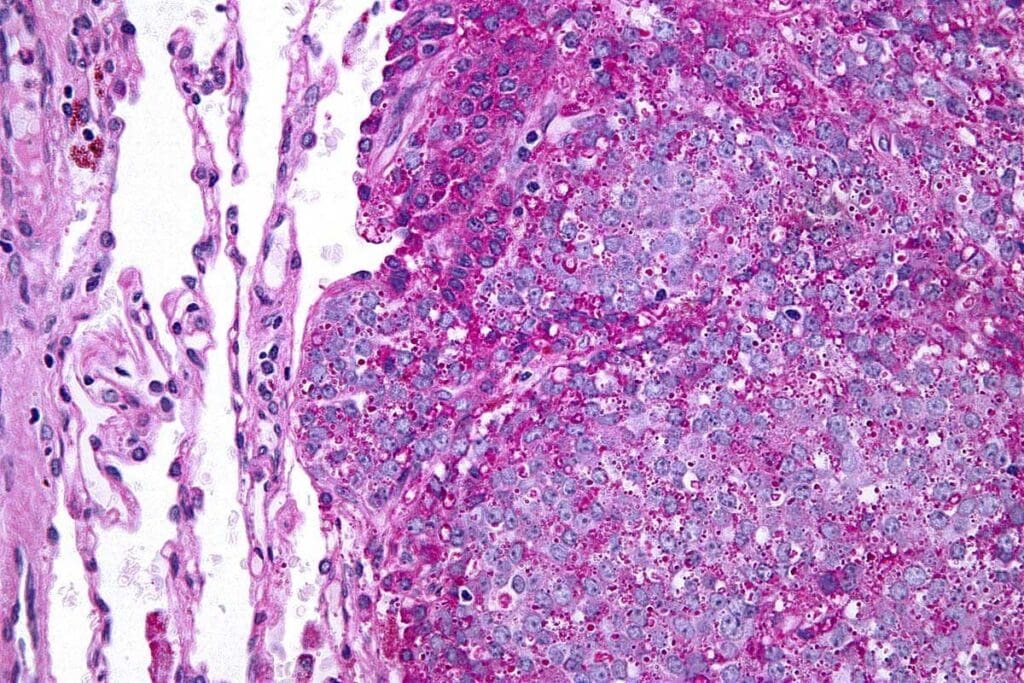

To confirm Ewing sarcoma, a biopsy is needed. This takes a tissue sample from the tumor for examination.

Molecular tests, like FISH and RT-PCR, look for specific genetic signs of Ewing sarcoma. These tests check for the EWS-FLI1 fusion, among others.

| Biopsy | Histological examination of tumor tissue |